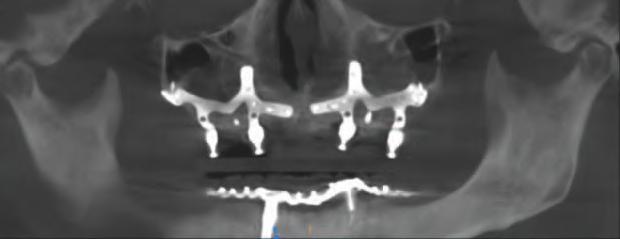

Implantur le subper ostale sunt structur metal ce fabr cate nd vdual pentru a se adapta ș a restab l zonele edentate. Personal zate ș concepute pentru a se potr v morfolog e osoase un ce a pac entulu , mplantur le subper ostale sunt plasate sub per ost ș sunt stab l zate pr n șurubur de f xare care ntră în contact cu osul sub acent ș țesutul f bros care le acoperă. Spre deoseb re de mplantur le convenț onale, mplantur le subper ostale se sprj nă d rect pe os ș prez ntă bontur care emerg pr n țesutur le g ng vale pentru a acomoda proteze f xe sau detașab le totale sau parț ale (un exemplu de implant subperiostal individualizat este ilustrat în fig. 6-14)

Protocolul debutează cu scanarea anatom e osoase a pac entulu folos nd tehnolog a CBCT, ar datele sunt ut l zate pentru o reconstrucț e v rtuală a max larulu edentat. Acestea sunt apo comb nate cu nformaț le d n scanăr le ntraorale ș modelele de ceară d agnost ce pentru a produce un model v rtual 3D cu scopul de a plan f ca corect des gnul mplantulu ș al proteze . Implantur le subper ostale moderne sunt de ob ce fabr cate pr n s nter zarea d rectă a metalulu cu laser (direct metal laser sintering, DMLS), proces în cadrul căru a un laser de